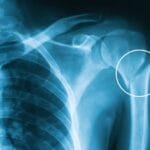

As you age, you naturally lose muscle and bone mass, which can lead to conditions like back pain, osteoarthritis, or osteoporosis. Regular exercise:- Slows muscle loss and strengthens bones.

- Improves mobility and balance, lowering the risk of falls and fractures.

Contrary to common fears, physical activity often improves chronic conditions rather than worsening them. For conditions like arthritis or osteoporosis, exercise is both safe and beneficial. Lack of movement can make these conditions more challenging to manage.